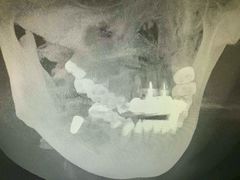

• TSK齿科德申会口腔门诊·联洋诊所

• -TSK齿科德申会口腔门诊·联洋诊所

金色罗盘 | 17-01-06

西瓜小菜菜的夏天 | 16-12-30